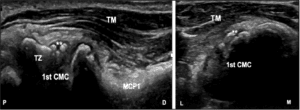

Infection of a Baker’s cyst is a very uncommon. The initial clinical suspicion of deep vein thrombosis or cellulitis is the most frequent clinical presentation [5]. The clinical signs suggestive of this infection are defined by a soft cyst, with a well-defined contour, located in the popliteal fossa and in the case of rupture, will lead to the appearance of a growing hematoma or anterior or distal ecchymosis of the lateral malleolus. Regarding diagnostic techniques, CT and magnetic resonance imaging (MRI) allow the cyst to be clearly defined, as well as to confirm rupture of the cyst along with any haemorrhagic complications, and whether it is accompanied by polymyositis or osteomyelitis. However, ultrasound can also easily detect a cystic structure in the popliteal fossa. Classically it can be identified as a well-defined cyst with a ‘neck’ at its deepest extent, extending into the joint space between the semimembranosus tendon and the medial head of the gastrocnemius. Identification of a fluid-filled structure at the posteromedial knee is suggestive of a popliteal cyst, but identification of the ‘neck’ between the tendons is necessary for a definitive diagnosis, the ‘neck’ has been described as being shaped like a “speech bubble” or “talk bubble” [6].